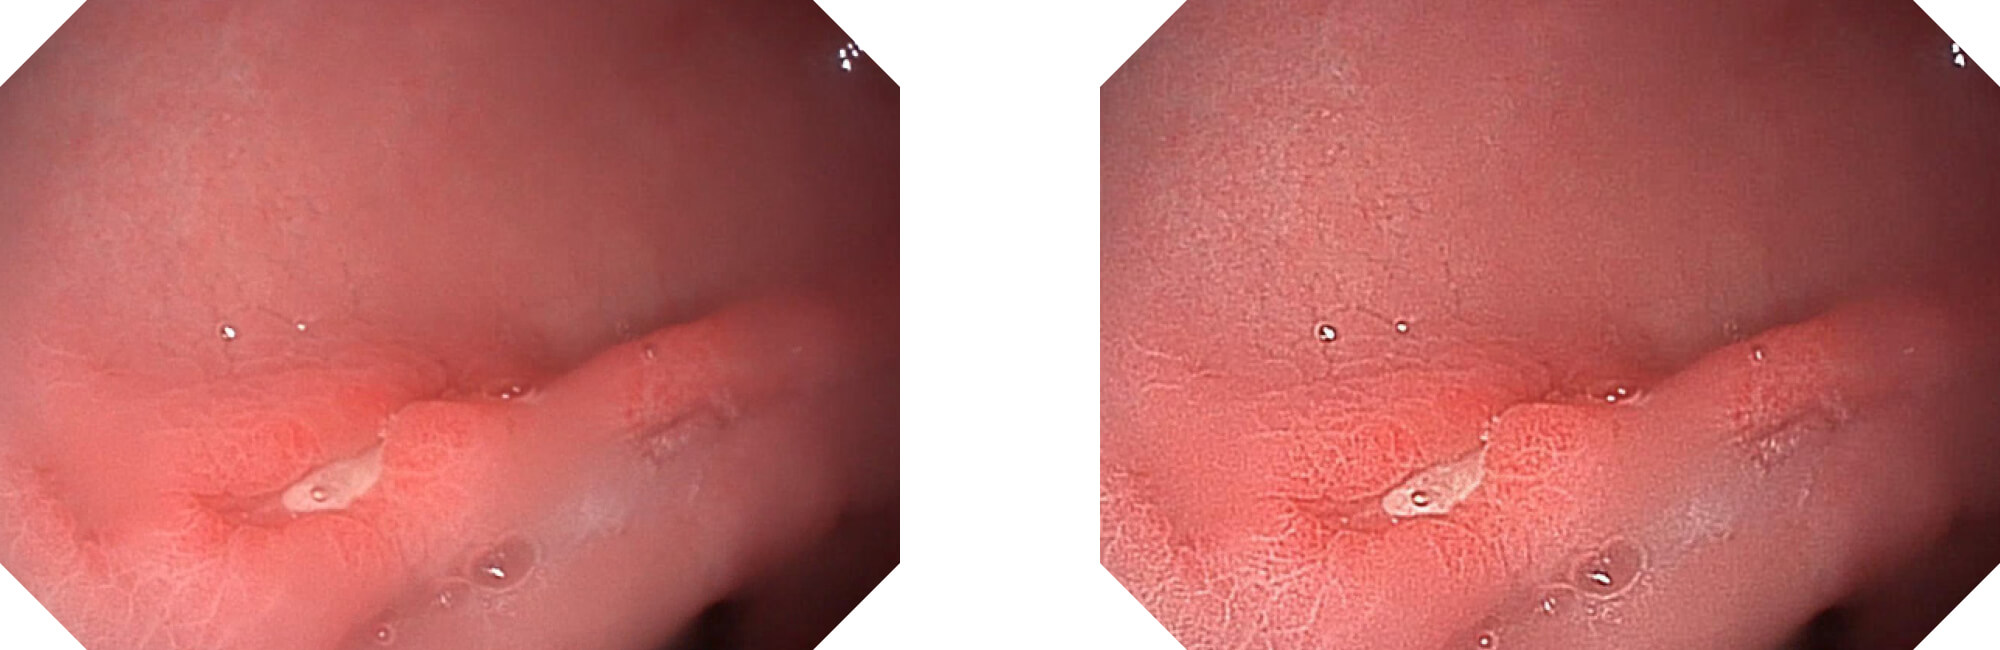

高清数字信号结合构造强调和色彩增强,多重图像处理技术能让每一个图像都清晰可见。

构造强调

色彩增强